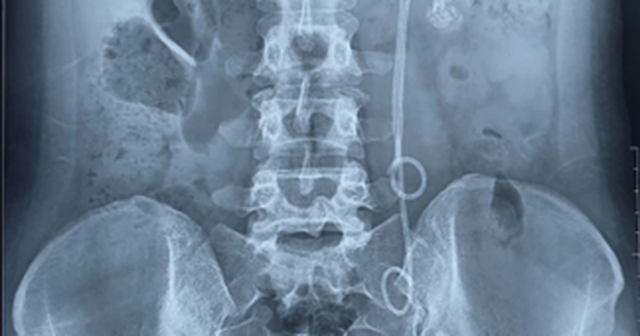

Người phụ nữ 33 tuổi đau tức thắt lưng, tiểu buốt, bác sĩ gắp ra thứ "đáng sợ" bên trong- Ảnh 1.

Hình ảnh XQ của bệnh nhân. Ảnh: Bệnh viện 19-8